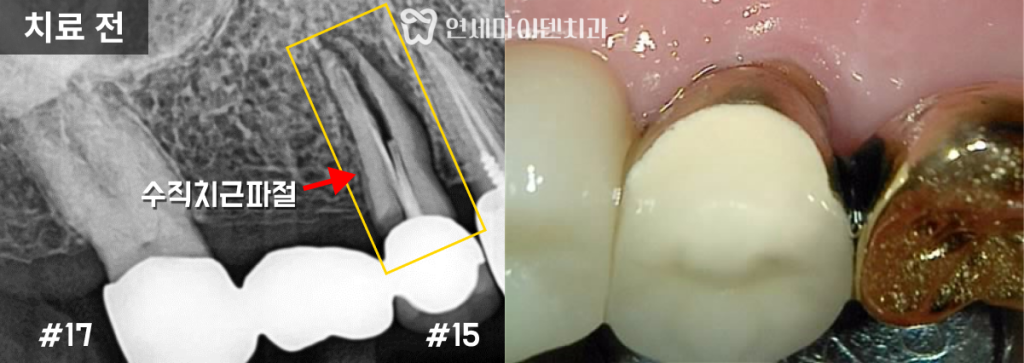

방사선 사진에서 브릿지의 한쪽 끝 치아 뿌리에

수직으로 금이 간 ‘수직치근파절‘을 확인했습니다.

뿌리까지 균열이 진행되어 사실상 치아가 깨진 상태였습니다.

금이 간 치아가 흔들리면서 반대편 고정치에 붙여진 브릿지도

틈이 생기고 접착제가 씻겨나가

시림 증상이 유발된 것으로 보였습니다.